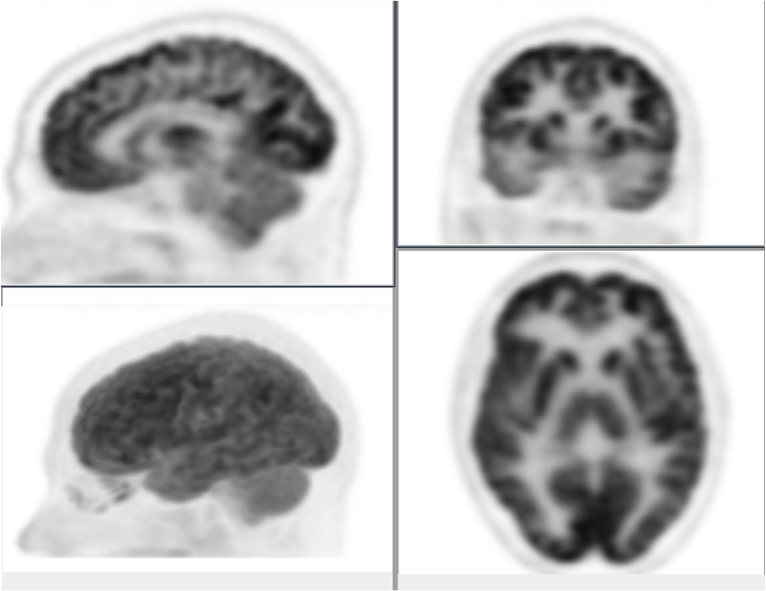

Included in the files are 2 pairs of brain scans. These represent the two comparisons between an older analogy technology and the breakthrough new digital technology from Philips.